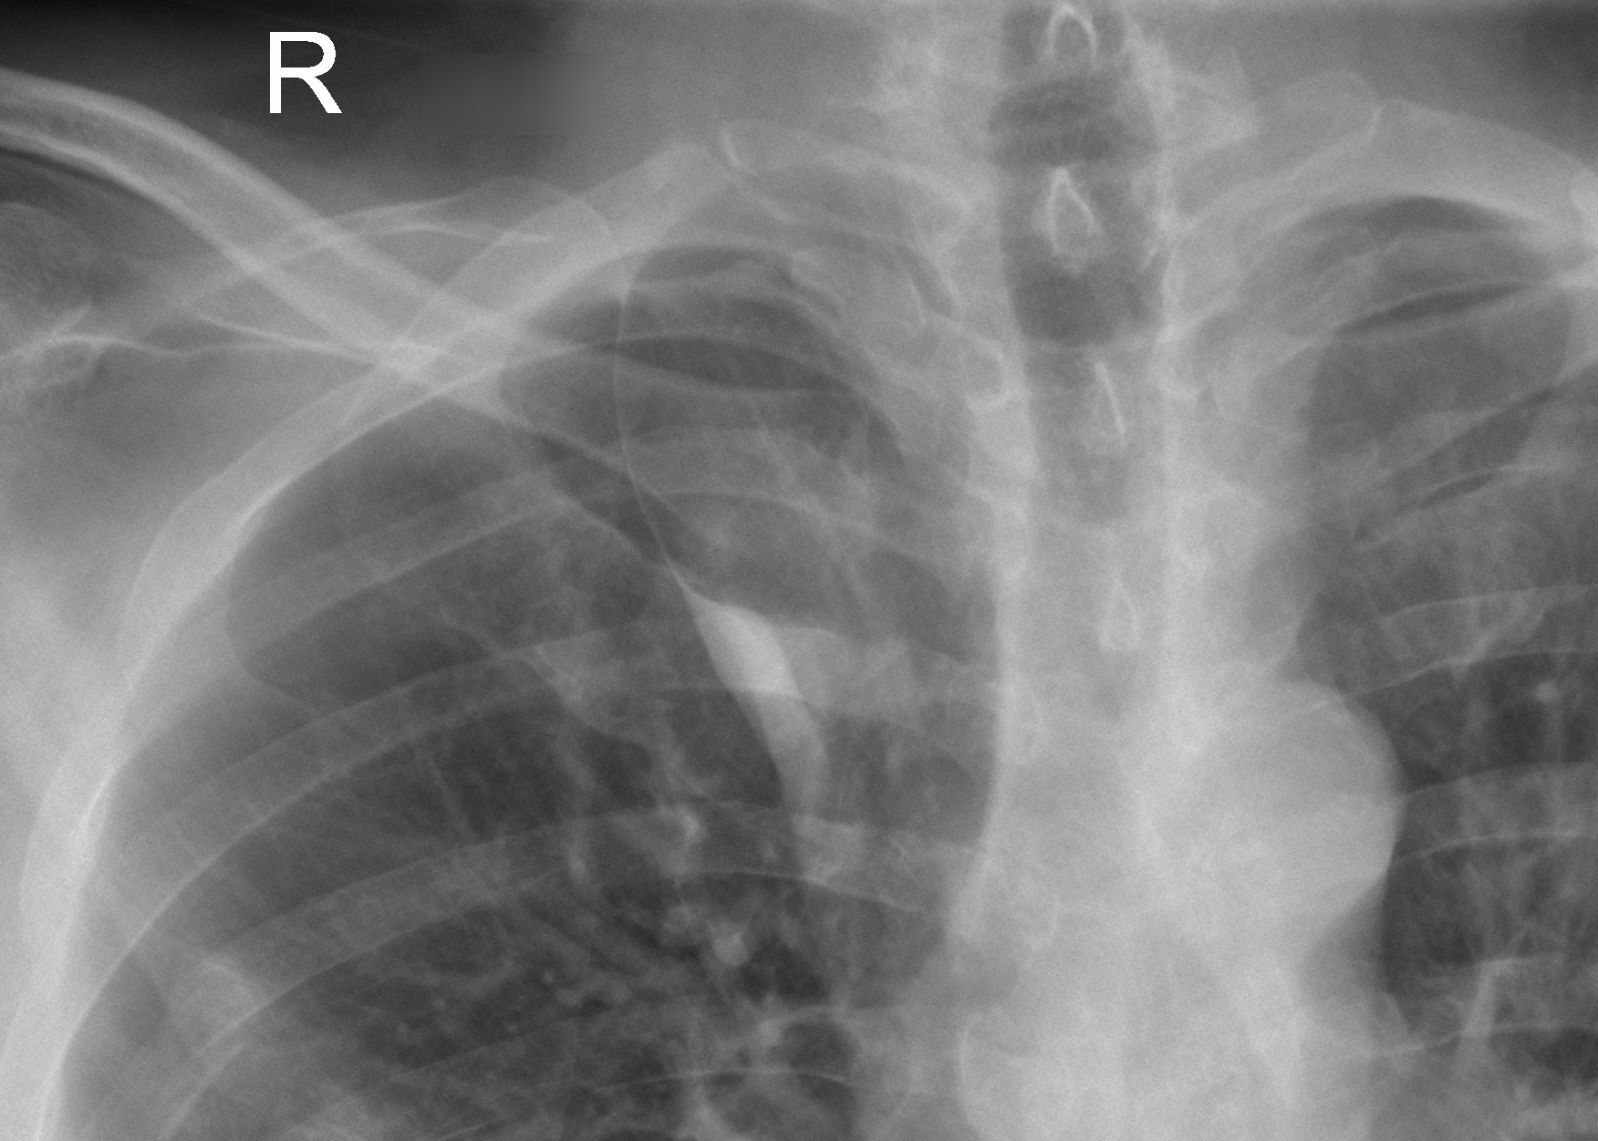

Фото: commons.wikimedia.org, Hellerhoff, Creative Commons Attribution-Share Alike 3.0 Unported license.